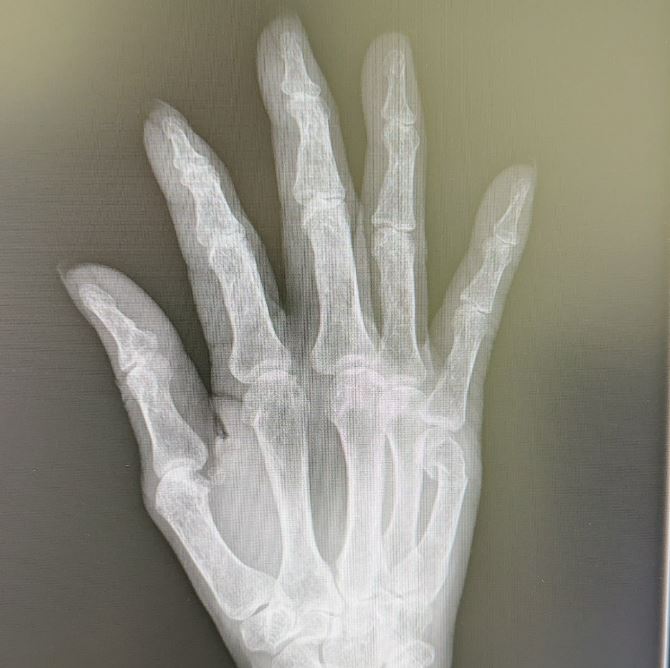

ブログには、整形外科を受診したときのことが記されていて、「昨日受診した○○整形外科の院長先生の治療には感動しました‼️」と書き出し「小指 第3関節の下 綺麗に折れてるのが 分かりますよね」「折れた骨が 内側に入り込んでるのが分かります」と骨折した指のレントゲン写真とともに説明。

そして「びっくり‼️真っ直ぐになってるーーー」「きゃーっ‼️‼️‼️驚きましたーーー‼️‼️‼真っ直ぐになってるーーー」と驚きの様子を綴っています。